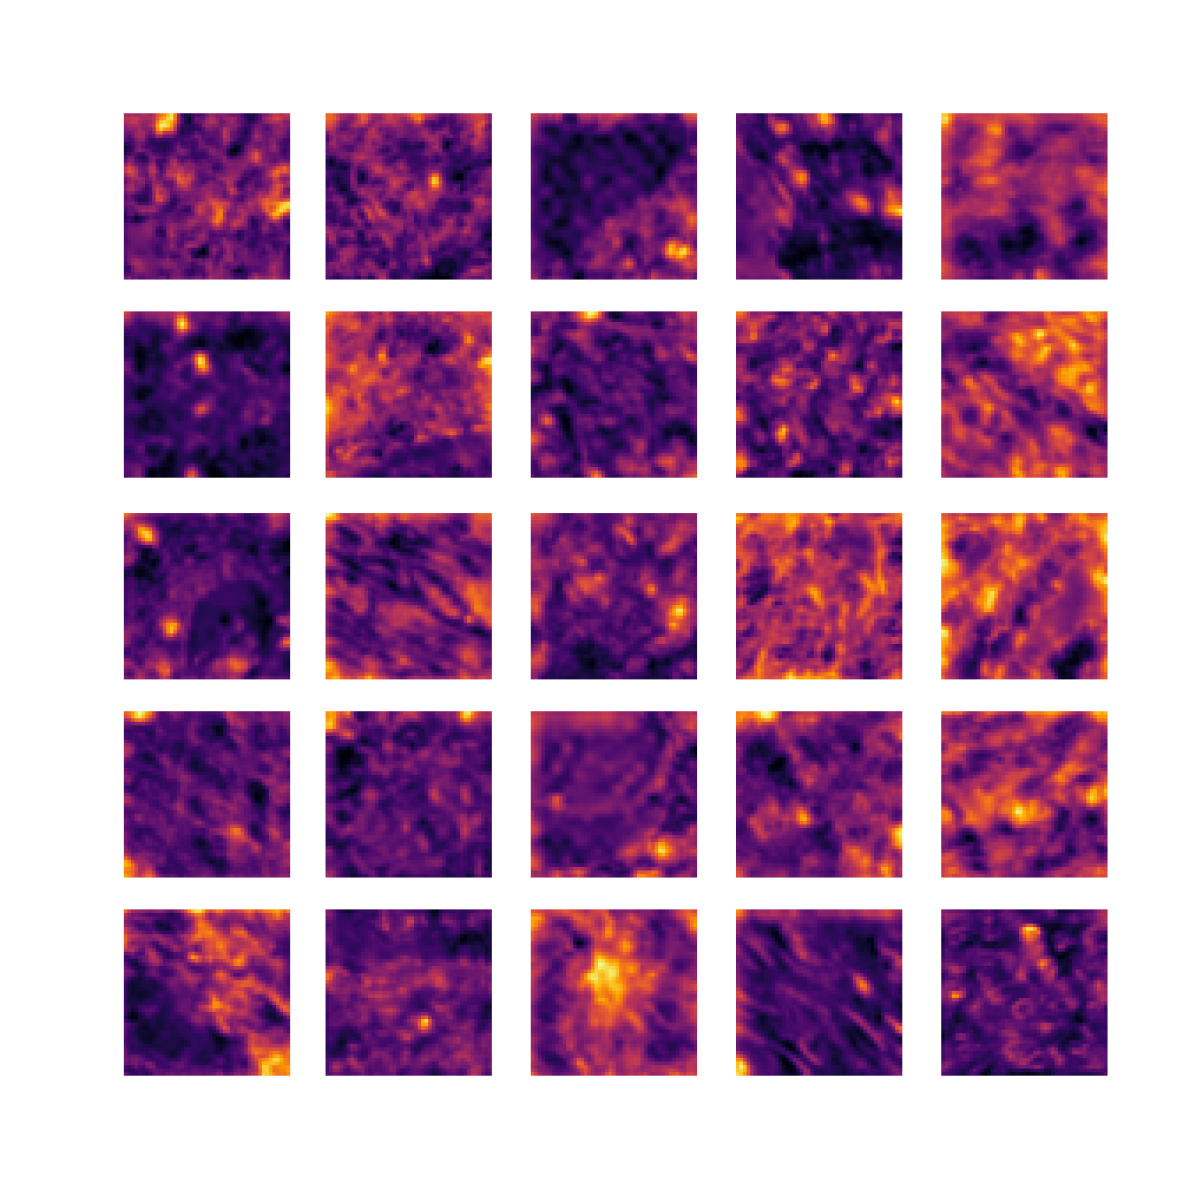

We also analyse the activation maps for each model using GradCAM as described in section S3. This offers more insight into the areas of the image which are contributing most heavily to the models’ representations. In Figure 4(b) we present some representative examples, however, a larger selection which was chosen at random is presented in Figures S10 to S25. The larger selection makes it easier to see the emergent patterns, including that privileged Siamese models tend to mainly identify features which are strongly present in both inputs, while unprivileged Siamese models tend to learn more diffuse features that are not specific to one cell phenotype or image region. TriDeNT ♆ incorporates both sets of features, learning both features specific to the privileged data and more the general features associated with unprivileged Siamese networks.

We can see in Figure 4(b) panel A that for ERG, the privileged Siamese model focuses almost exclusively on any nuclei which could be endothelial cells. As there are very few endothelial cells in the dataset, it could be an effective strategy to identify anything that could potentially be an endothelial cell to minimise the difference between the representations of the H&E model and the IF mask model. In the corresponding unprivileged Siamese image, we see that the model identifies some of these nuclei, albeit less strongly, but also focuses heavily on the other tissue and even the background, while strongly fixating on two spots of debris in the center of the image. This model has less ‘incentive’ to learn the weak features related to endothelial cells as these occur rarely and are not easy to detect, while more generic strong features such as the presence of connective tissue and the prevalence of background are more common and predictable from augmented images. We see that TriDeNT ♆ combines these two feature sets, strongly identifying nuclei while also identifying the connective tissue.

In panel C we see a similar pattern, with the privileged Siamese model fixating solely on the nuclei, while the TriDeNT ♆ model takes a more balanced approach. The unprivileged Siamese model appears to focus on a single cluster of nuclei while neglecting others, and similarly identifies an area of fibroblasts with its distinctive pattern but does not others.

In contrast to panels A and C which represent models with poor privileged Siamese results, panels B and D represent models whose privileged Siamese results were comparable to both TriDeNT ♆ and even the supervised baseline. It is therefore interesting to note that there are far more similarities between the privileged Siamese and TriDeNT ♆ models in both cases. Particularly in panel B, TriDeNT ♆ and the privileged Siamese model return virtually identical heatmaps, with both strongly identifying epithelial nuclei and neglecting the same areas of connective tissue. The unprivileged model in this case appears to focus solely on the centre of the image, giving a significantly different heatmap to the other panels.

Panel D again shows the previous pattern, with the privileged Siamese model identifying the features strongly present in the privileged data – fibroblasts – while neglecting the nuclei present. TriDeNT ♆ also strongly identifies the connective tissue, but, unlike the privileged Siamese model, does not completely neglect the nuclei. The unprivileged Siamese model primarily identifies background, and does not appear to identify the nuclei in this example.